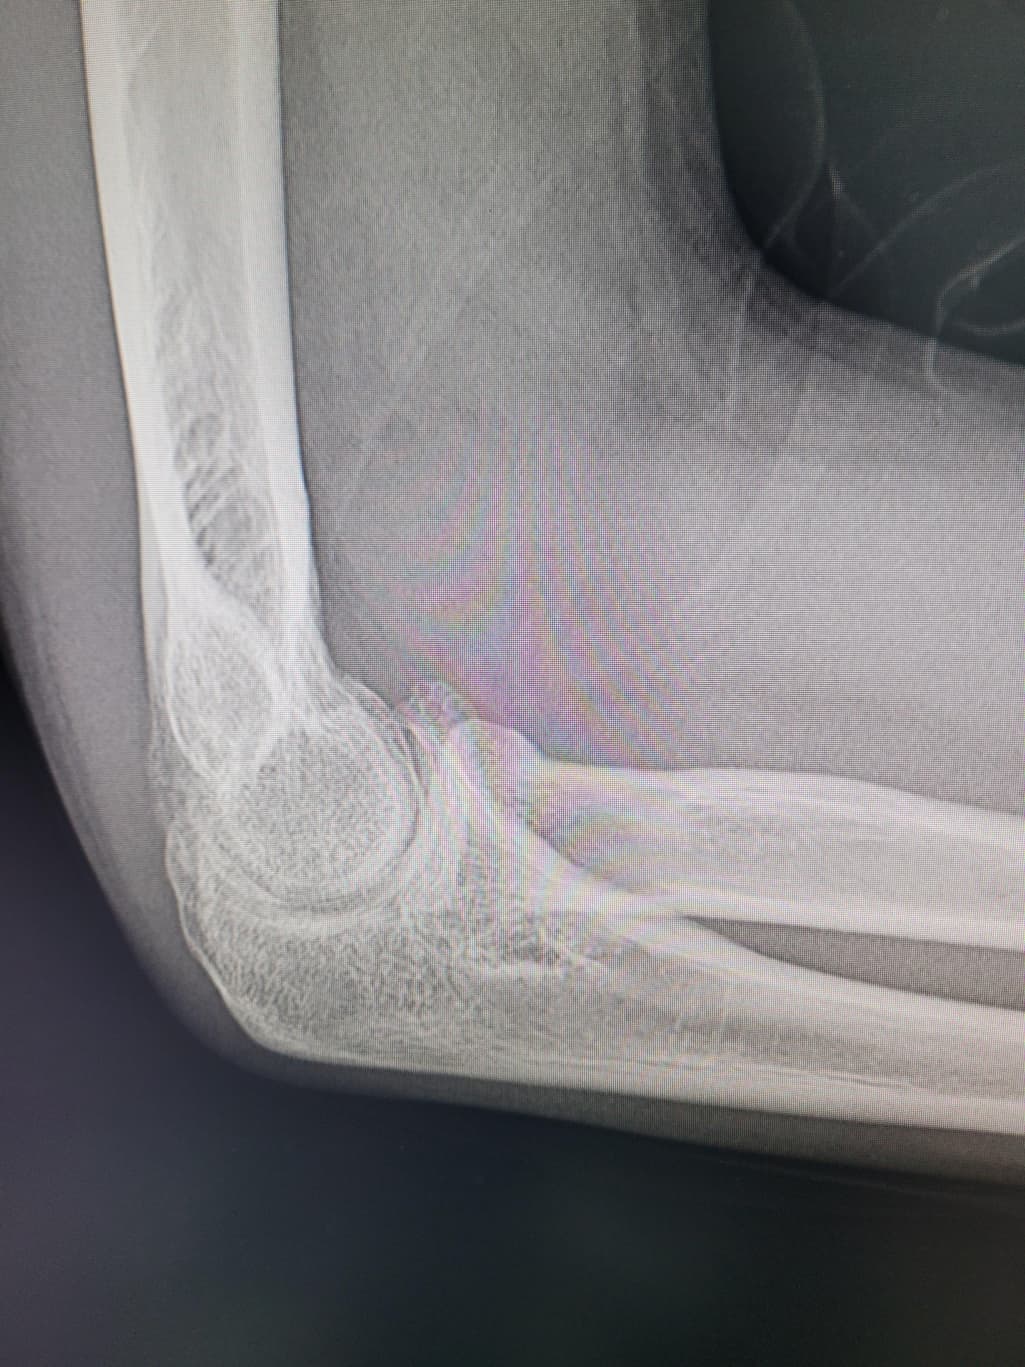

팔이 아파서 여러병원 찾아다니느라 엑스레이 사진도 복사해왔는데 1,2년 전에 비해서 팔꿈치에 동그란 게 생겼더라구여 이게 뭔지 모르겠습니다

활액막연골종은 일반적으로 엑스레이에서 뼈의 경계가 부풀어 오르거나 변형된 모습이 나타날 수 있습니다.

엑스레이에서 종양은 종종 비정상적인 경계와 불규칙한 모양을 보입니다 뼈의 구조와 혼합된 모습 일 수 있습니다.

정확한 진단을 위해 엑스레이 외에도 MRI, CT촬영과 같은 추가 검사가 필요 할 수 있습니다 전문의와 상담하는 것이 좋을 것 같습니다.

구조상 큰 변화는 없어 보입니다. 그러나, 정확한 소견은 전문의의 판독결과를 들어보시는 것이 가장정확하고, 연부조직의 염증같은 경우에는 엑스레이 보다는 초음파나 MRI와 같은 검사방법이 정확한 검사를 시행할 수 있겠습니다. 주치의와 상의 후에 판독결과나 추가적인 검사등에 대한 상담을 받아보시고, 필요시에는 검사를 받으시는 것이 좋겠습니다.